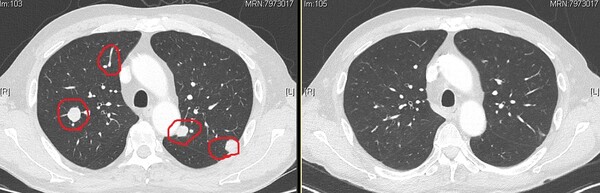

“왼쪽이 처음 우리 병원에 왔을 때 CT사진입니다. 커다란 암세포가 3개 정도 있었고 이외에도 신장 전체에 하얀 암세포들이 퍼져있는 것을 볼 수 있죠. 그런데 면역항암제를 1년 6개월 가량 투여하고 오른쪽 사진처럼 일부 암세포들은 완전히 없어졌어요. 퍼져있던 암세포들도 많이 줄어있습니다.”

원주세브란스기독병원 임승택(혈액종양내과) 교수는 자신이 치료하고 있는 신장암 환자의 CT사진을 보여주며, 옵디보(니볼루맙)-여보이(이필리무맙) 병용요법 같은 면역항암제 효과가 정말 놀랍다고 했다. 임승택 교수는 현재 원주세브란스기독병원에서 신장암을 포함해 비뇨기암 분야를 전문으로 하는 유일한 혈액종양내과 전문의다.

지난 2021년 10월 임승택 교수를 찾아온 58세 A씨(남성)도 평소 아무런 증상이 없어 자신이 암에 걸렸을 것이라고는 꿈에도 생각 못했다. 건강검진을 받다가 신장에 혹이 발견돼 정밀검사를 받은 뒤에야 암이라는 것을 알았다. 하지만 이미 그는 폐를 포함해 다발성으로 전이된 신장암 4기였다. 신장암 중에서도 예후가 제일 안 좋다는 ‘투명세포 신장암(Clear Cell Carcinoma)’이다.

“신장암 중에서도 투명세포 신장암은 일반 항암화학요법이나 방사선 치료에 잘 반응하지 않기 때문에 예후가 불량한 것으로 알려져 있어요. 그 중에서도 이 환자는 고위험군에 속해 불량한 예후가 예상됐죠. 하지만 옵디보-여보이 병용요법으로 치료를 시작한 이후 종양이 확연히 줄어들었어요. 투약한 지 1년이 지난 현재까지 치료 반응이 잘 유지되고 있습니다.”

‘옵디보-여보이 병용요법’은 투명세포암으로 IMDC 위험도 중등도 또는 고위험군인 진행성 신세포암의 1차 치료제로 지난 2021년 9월 건강보험이 적용됐다. 급여적용 기간은 최대 2년이며, 옵디보-여보이 병용투여는 3주 간격으로 4회 실시하고 그 이후에는 옵디보 단독요법으로 몸무게에 따라 용량을 달리해 2주 간격으로 투여한다. A씨는 옵디보-여보이 병용투여 4회, 옵디보 단독요법으로 27회차까지 마쳤다.